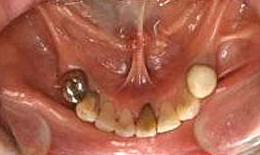

インプラント症例(2) 61歳 女性

治療方法

- 上顎

- 義歯を作製

- 下顎

- インプラントを5本埋め込み、セラミックスクラウンを被せた